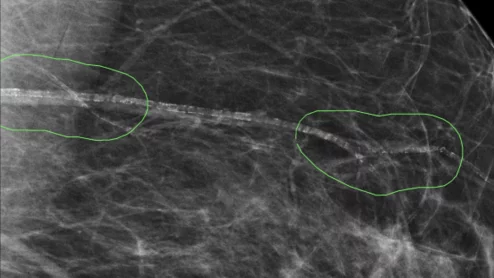

Thanks to AI, clinicians can use mammograms to do a lot more than identify signs of breast cancer. Researchers explored data from nearly 50,000 patients, presenting their findings in Heart.